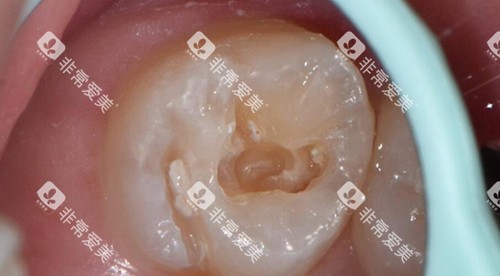

3. 特殊场景:深龋或复杂修复

若龋坏接近牙髓,需垫底或安抚治疗,费用增加100-300元/颗;若涉及牙体大量缺损,需分层堆塑树脂,操作时间延长,费用可能上浮20%-50%。